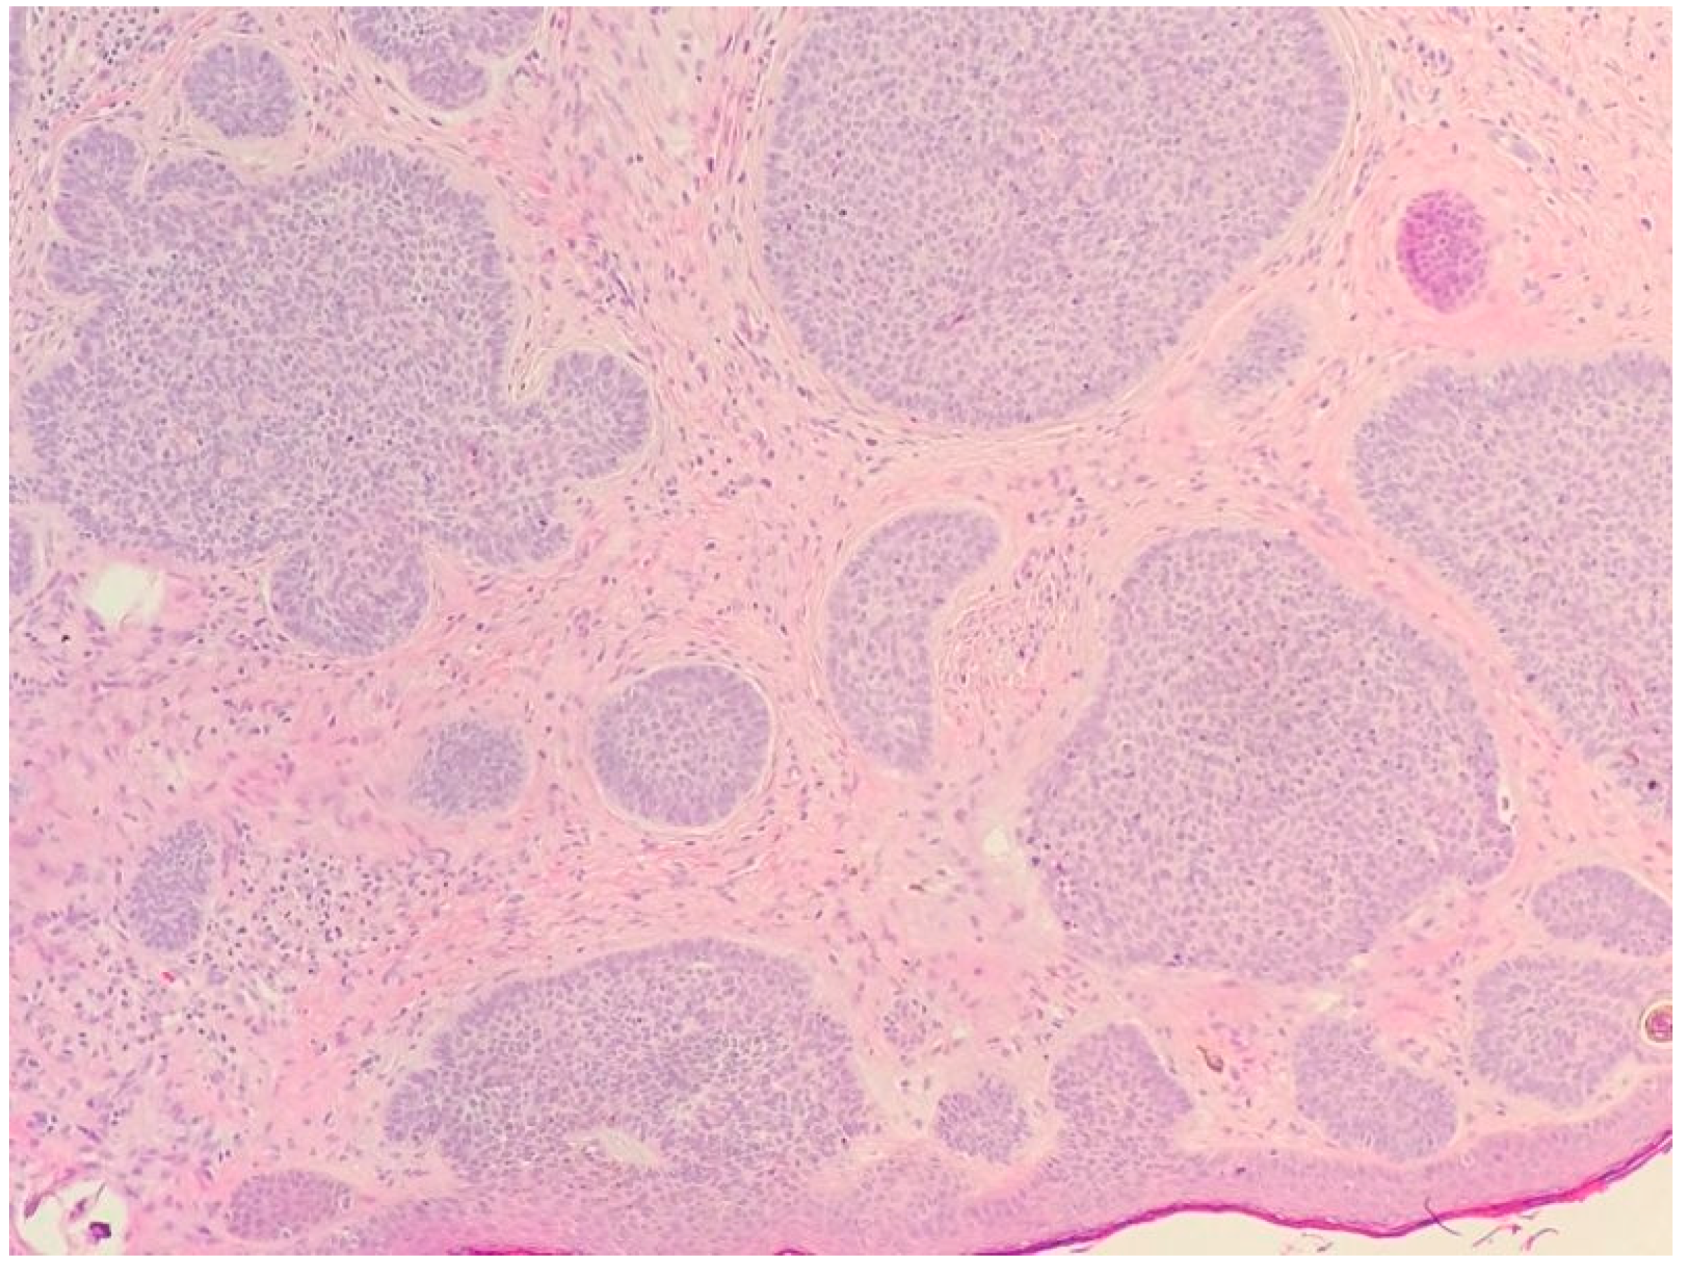

2.1. Basal Cell Carcinoma and Its Histological Variants

2.1.2. Main Histologic Variants